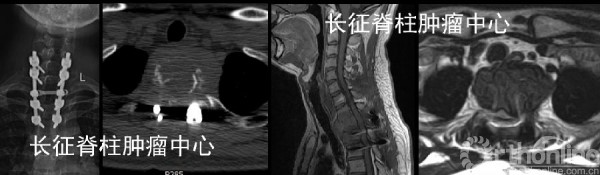

第一次术前CT、MRI均提示胸2椎体溶骨性破坏。

当地医院行后路胸2椎体次全切除取髂骨植骨重建内固定术,术后5月,X线,CT及MRI均提示胸1-3椎体溶骨性破坏,考虑胸2肿瘤组织残留、复发并侵及邻近椎节。